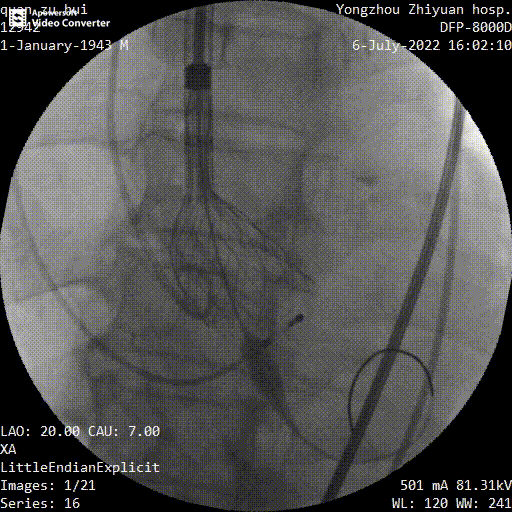

释放到工作位

多角度观察

最终释放

手术过程中,在完成跨瓣操作后,23mm球囊预扩有轻微腰征、无造影剂渗漏,预装TaurusElite AV29瓣膜到位,输送系统快速、顺利地完成过弓、跨瓣操作,于瓣环上约2mm定位释放;针对本例患者瓣叶明显增厚伴重度钙化,左右窦间可见钙化融合嵴的特点,TaurusElite瓣膜高密度流入端设计提供了足够的径向支撑力,保证了瓣膜的锚定力,瓣膜内外双裙边设计能提供良好的辅助锚定力,有效减少瓣周漏。此外,本例患者左窦间存在长条状钙化延伸至瓣环下10mm水平,释放位置偏深可能存在起搏器植入风险,TaurusElite瓣膜具有多次完全可回收,回收后可重新跨瓣、释放的特点,给予术者足够的信心完成高位释放的操作,释放后最终瓣架底端位于瓣环下约1mm,实现了释放位置的精准控制,有效的减少了起搏器植入风险,确保了手术安全、顺利的完成。这例手术为永州地区开展的第一台TAVR手术,填补了该地区TAVR技术空白,标志着永州市心脏瓣膜疾病诊治迈入了全新的微创治疗时代!